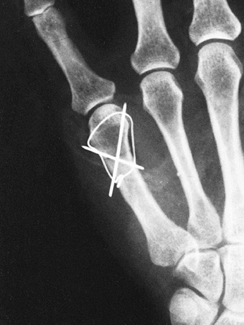

looped with a stainless-steel wire as a tension band (Fig. 40.9).

Figure 40.9.

A 46-year-old woman was thrown from a horse, sustaining multiple

injuries. Anteroposterior radiograph shows a fifth metacarpal neck

fracture treated by two crossed Kirschner wires and a dorsal

stainless-steel loop acting as a tension band. -